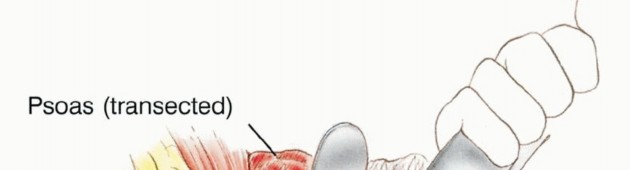

The psoas muscle and femoral nerve are then transected high in the pelvis.

The procedure begins with an ilioinguinal incision. The abdominal musculature is detached from the iliac crest and the inguinal ligament. The peritoneum is bluntly swept medially to expose the retroperitoneal space. The ureter is identified and retracted medially with the peritoneum. The major vascular structures are isolated.

* For a Classic Hemipelvectomy, the common iliac artery and vein are doubly ligated and divided.

* For a Modified Hemipelvectomy, the internal iliac (hypogastric) artery is carefully preserved, and the external iliac artery and vein are ligated.